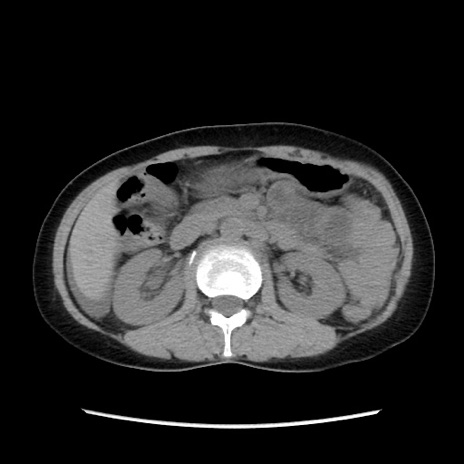

冠状断像